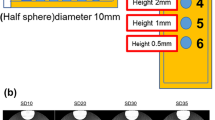

All axial images were transferred to an AW 4.7 (GE HealthCare, Milwaukee, WI, USA) workstation for the following reformatted images: two-dimensional (2D) Multi-planar Reformation (MPR), three-dimensional (3D) endoluminal view from CT Virtual Colonoscopy (CTVC) and 3D Raysum. On the axial images, the circular regions of interest (ROIs) were drawn on the homogenous area of the colorectal tumor and intraluminal air to measure the CT value and the standard deviation (SD) values, in order to calculate the signal-to-noise ratio (SNR) and the contrast-to-noise ratio (CNR) of tumors. The formulas were as follows: SNR=CT tumor/SD tumor, CNR=(CT tumor-CT intraluminal air)/SD intraluminal air. The tumor ROIs were depicted on the slice of maximum diameter, and were manually placed on the prone and supine images, keeping the ROI size accounting for 70-80% of the tumor. The measurements on three consecutive slices were recorded and averaged to avoid measuring bias, and the ROI sizes ranged from 50 to 100 mm2.